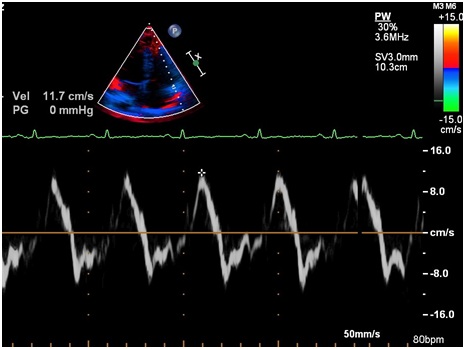

Ürəkdə hər hansı struktur dəyişlikliyin olub olmadığını bilmək üçün 2D, M, TDI-PW rejimlərindən istifadə etməklə exokardioqrafik müayinə aparıldı. Müayinə zamanı sağ mədəciyin (RV) sərbəst divarında çapıq toxumasına bənzər hiperexogen sahə, sağ mədəciyin genəlməsi və sistolik funksiyasının zəifləməsi (FAC – 30.5%, N > 35%) aşkarlandı (şəkillər 2-8). Bunun ardınca təyin olunan EKQ-nin 24 saatlıq Holter monitorlamasında çoxlu miqdarda (politop, qrupşəkilli, triplet) mədəcik ektopiyası qeydə alındı (şəkil 9). Bu nəticələrə asasən xəstədə aritmogen sağ mədəcik displaziyasına (ARVD, ARVC) şübhə yarandı və ürəyin MRT olunmasına qərar verildi. Ürəyin MRT müayinəsində aritmogen displaziyaya uyğun görüntülər qeydə alındı.